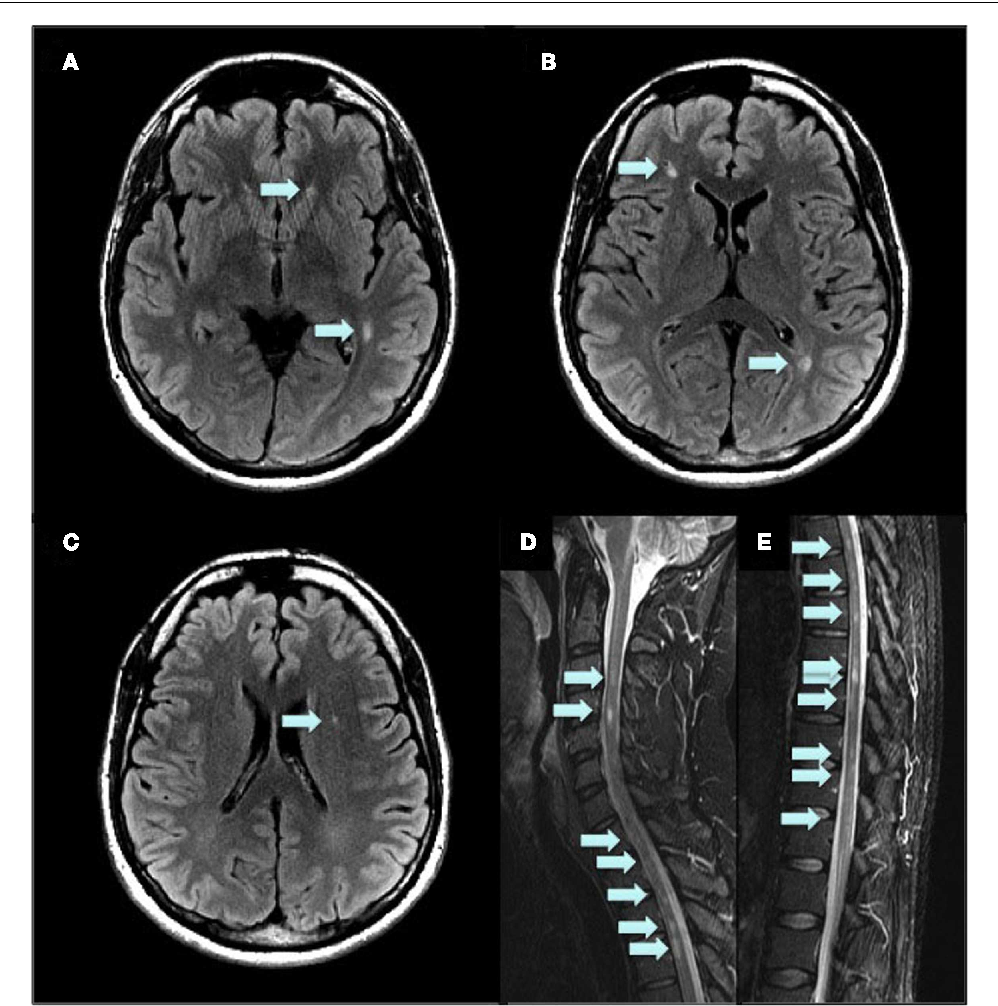

Fazekas grades. ЦАДАСИЛ CADASIL. ЦАДАСИЛ мрт. Шкала Фазекас мрт. Микроангиопатия мозга на кт.

Fazekas grades. ЦАДАСИЛ CADASIL. ЦАДАСИЛ мрт. Шкала Фазекас мрт. Микроангиопатия мозга на кт.

Fazekas grades. Амилоидная микроангиопатия. Церебральная микроангиопатия мрт. Дегенеративная микроангиопатия. Гипертензивная микроангиопатия мрт.

Fazekas grades. Амилоидная микроангиопатия. Церебральная микроангиопатия мрт. Дегенеративная микроангиопатия. Гипертензивная микроангиопатия мрт.

Fazekas grades. Лейкоареоз Фазекас. Fazekas 0. Фазекас 3. Фазекас классификация мрт.

Fazekas grades. Лейкоареоз Фазекас. Fazekas 0. Фазекас 3. Фазекас классификация мрт.